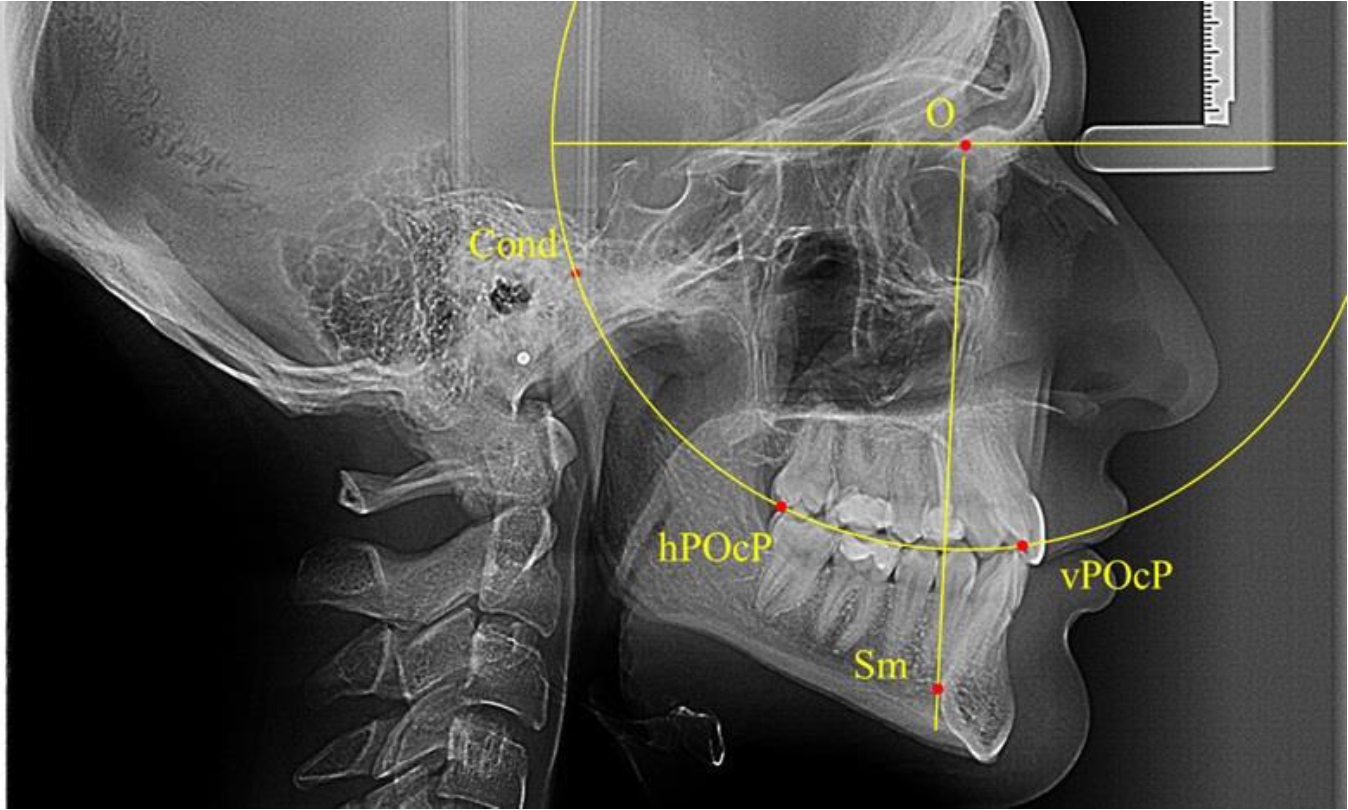

Анализ снимков проводили с использованием традиционного построения стресс-оси по Bimler. Для удобства построения использовали компьютерную программу PowerPoint. Основными точками для построения круга были передняя (vPOcP) и дистальная (hPOcP) окклюзионные точки, а также верхняя выпуклость суставной головки (Cond).

Вставка из программы в виде овала накладывалась на фотографию рентгенограммы и ручным способом растягивалась так, чтобы получился круг, проходящий через обозначенные реперные точки.

Центр окружности О, соединяющей точку резцового перекрытия с жевательной поверхностью зубов и серединой суставных головок, соединяли с выступающей точкой Sm на внутреннем контуре подбородка (рис. 1).

Рис. 1. Метод анализа ТРГ по Bimler

В норме, по резульатам исследования автора, линия Bimler проходила по вертикальной оси первых премоляров, что мы также расценивали как оптимальное их расположение.